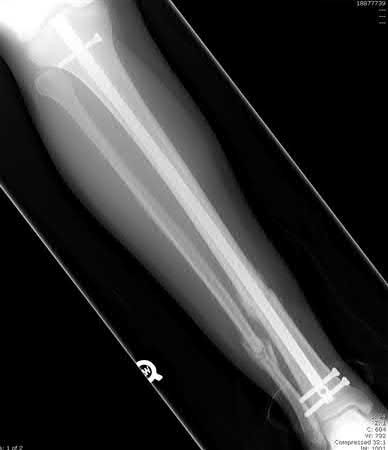

1. # A 32-year-old male sustains the injury shown in Figure A and undergoes treatment as shown in Figure B. Following placement of this implant, what is the best technique to confirm it is not too proud proximally?

The safe zone for tibial nail placement as seen on radiographs is just medial to the lateral tibial spine on the anteroposterior radiograph and immediately adjacent and anterior to the articular surface as visualized on the lateral radiograph.

Tornetta et al specifically located the safe zone for nail entry in a study using fresh frozen cadaver knees. The authors found that the safe zone for nail placement is located 9.1+/-5 millimeters lateral to the midline of the plateau and three millimeters lateral to the center of the tibial tubercle. The width of the safe zone averaged 22.9 millimeters and was as narrow as 12.6 millimeters.

The starting point of the of the nail can be best viewed on the lateral knee radiograph, an example of which is shown in Illustration A. Illustration B shows the "sweet spot" for nail insertion as defined by Tornetta.